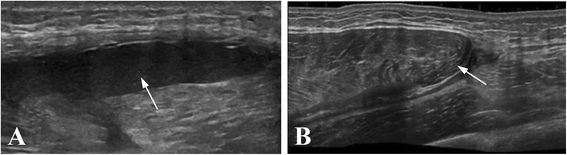

Methods: Twenty-four rats were divided into a control group, Notexin group (7 and 14 days) and a Notexin + EPI group. To induce muscle injury, Notexin was injected in the quadriceps of the left extremity of rats. Pro-inflammatory interleukin 1-beta (IL-1beta) and tumoral necrosis factor-alpha (TNF-alpha) were determined by ELISA. The expression of receptor peroxisome gamma proliferator activator (PPAR-gamma), vascular endothelial growth factor (VEGF) and vascular endothelial growth factor receptor-1 (VEGF-R1) were determined by western-blot.

Results: The plasma levels of TNF-alpha and IL-1beta in Notexin-injured rats showed a significant increase compared with the control group. EPI® produced a return of TNF-alpha and IL-1beta values to control levels. PPAR-gamma expression diminished injured quadriceps muscle in rats. EPI® increased PPAR-gamma, VEGF and VEGF-R1 expressions. EPI® decreased plasma levels of pro-inflammatory TNF-alpha and IL-1beta and increased anti-inflammatory PPAR-gamma and proangiogenic factors as well as VEGF and VEGF-R1 expressions.

Conclusion: The EPI® technique may affect inflammatory mediators in damaged muscle tissue and influences the new vascularization of the injured area. These results suggest that EPI® might represent a useful new therapy for the treatment of muscle injuries. Although our study in rats may represent a valid approach to evaluate EPI® treatment, studies designed to determine how the EPI® treatment may affect recovery of injury in humans are needed.